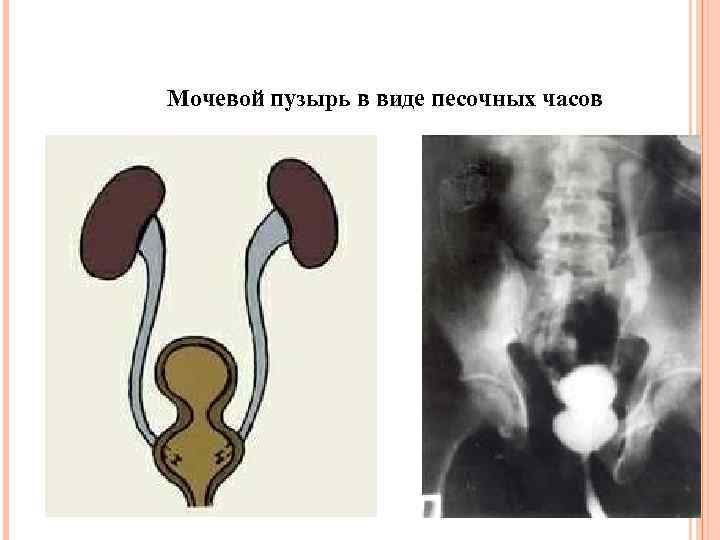

Мочевой пузырь в виде песочных часов

Мочевой пузырь в виде песочных часов